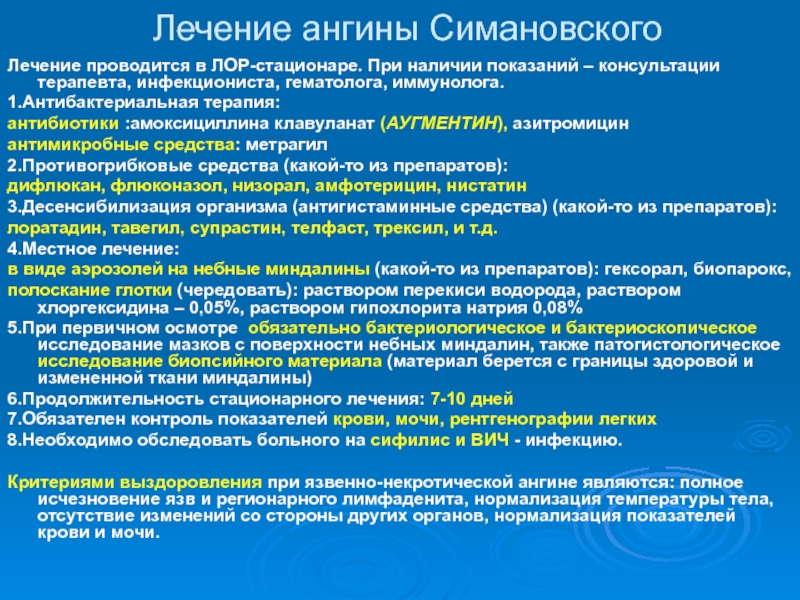

Процесс лечения лакунарной ангине

В первую очередь, пациенту назначается постельный и питьевой режим. Лакунарная ангина у взрослых лечится при помощи сульфаниламидных препаратов и ацетилсалициловой кислоты. Средства, понижающие температуру, необходимо принимать при температуре выше тридцати восьми градусов.

Также лечебный процесс включает.

- Прием антибиотиков. Зачастую лечение заболевания проводится в домашних условиях. Обязательным условием терапии являются антибиотики при лакунарной ангине. Они позволяют быстрее восстановиться пациенту и вовремя устранить возбудителя. Длительность лечебного курса составляет от пяти до десяти дней в зависимости от тяжести болезни. Также прием антибиотиков позволяет снизить вероятность возникновения осложнений. Взрослым назначают такие средства, как Сумамед, Азитромицин, Флемоксин Солютаб.

- Применение противовирусных средств. Назначаются в том случае, ангина была вызвана вирусами. Тогда лечение включает прием средств в виде Циклоферона, Амиксина, Кагоцела.

- Местное лечение болезни. Данный метод является обязательным условием терапии. Полоскания и орошения горла направлены на дезинфекцию полости и уменьшению симптоматики. К самым эффективным местным средствам относят: полоскания горла раствором Фурацилина, содовым и солевым раствором с йодом.; полоскания настоями лекарственных трав в виде ромашки, календулы, шалфея; орошение горла раствором морской соли; орошение горла лекарственными средствами в виде Мирамистина, Гексорала, Каметона; рассасывание противовоспалительных и антибактериальных таблеток в виде Граммидина, Стрепсилса, Лизобакта, Фарингосепта.

Если проявилась лакунарная ангина у детей, то лечение включает прием антигистаминных средств в виде Зодака, фенистила, Эриуса. Такие препараты способствуют снятию отечности миндалин и глотки. При высокой температуре детям рекомендуют ставить свечи Цефекон или давать Парацетамол и Ибупрофен в сиропе.

Также в детском возрасте обязательно назначают антибиотики в виде Амоксиклава, аугментина или Флемоксина. Наряду с этим нужно принимать средства, которые нормализуют микрофлору кишечника.

Так как дети до определенного возраста не имеют полоскать горло, то вместо этого стоит проводить орошение горла настоями лекарственных трав и раствором Фурацилина. Также можно использовать Мирамистин. Для повышения иммунных сил детям назначают свечи Виферон или таблетки Анаферон.